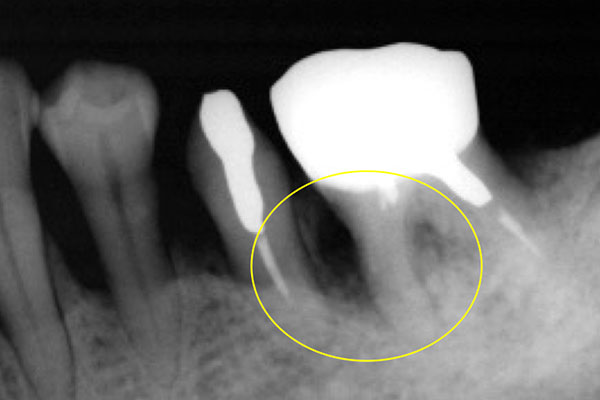

歯周病が進行して、歯の根元まで炎症が広がることがあります。右の写真をご覧ください。赤丸で囲んだ分が黒くなっています。ここは、歯肉が衰え、歯と歯肉の間にできたすき間です。ここに付着した歯石を取り除くことはできません。放置すると歯周病がさらに進行して、やがて抜歯となってしまうでしょう。

そこで、外科的手術で歯の根を露出させて歯石を取り除きます。さらに歯の根の間に歯間ブラシが入るように穴をあけ、お手入れしやすくします。この術式を「トンネリング」といいます。